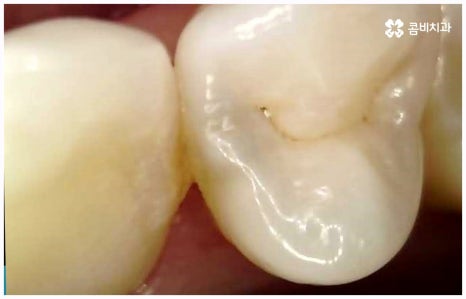

사람의 치아는 유치에서 영구치로 바뀌고 나면 다시 새롭게 나지 않기 때문에 만약 충치 등 구강 질환이나 노환, 외부 사고로 인해 치아를 잃게 되면 이를 대체해 줄 필요가 있습니다. 저작 기능을 담당하고 있기 때문에 치아가 없으면 매일 식사를 할 때 불편함이 크고 발음이 부정확해 질 수도 있으며 양치질을 할 때도 음식물 찌꺼기가 잘 끼는 등 위생 문제가 생길 가능성도 있어요. 또한 앞니 같이 잘 보이는 위치에 있는 치아를 상실하였을 경우 심미적으로도 자신감이 떨어질 수 있는데다 치아 상실 후 시간이 오래 지나도록 그대로 방치하게 되면 주변 치아들이 해당 부위 쪽으로 기울어지게 되고 잇몸뼈 역시 흡수가 일어나기 시작하기 때문에 옆 치아도 내려가면서 치열이 불규칙하게 바뀔 수 있습니다. 결국 심한 경우 상악과 하악의 불균형 및 안면비대칭까지 유발할 수 있기 때문에 치아가 빠졌을 때는 인공 치아를 통해 기능적 심미적인 대체를 해 줄 필요가 있는데요.

이러한 치아 상실에 대해 예전에는 틀니와 브릿지 시술을 많이 받았지만 요즘 대세는 임플란트 식립이라고 할 수 있어요. 틀니처럼 탈락의 위험이 잦거나 음식을 먹을 때 제약이 크게 따르지 않으며 브릿지처럼 양 옆 치아를 제거하지 않아도 되는 임플란트는 치아가 빠진 잇몸에 직접 티타늄 인공 치근(픽스처)을 심은 다음 지대주(연결 부위)를 이어주고 크라운(치아 머리 보철물)을 씌워 수복을 하는 것이기 때문에 저작 능력의 회복이 탁월하고 겉에서 봤을 때 거의 자신의 치아와 다름없이 자연스럽게 보인다는 장점으로 인해 많은 분들이 선호하시는 거예요.